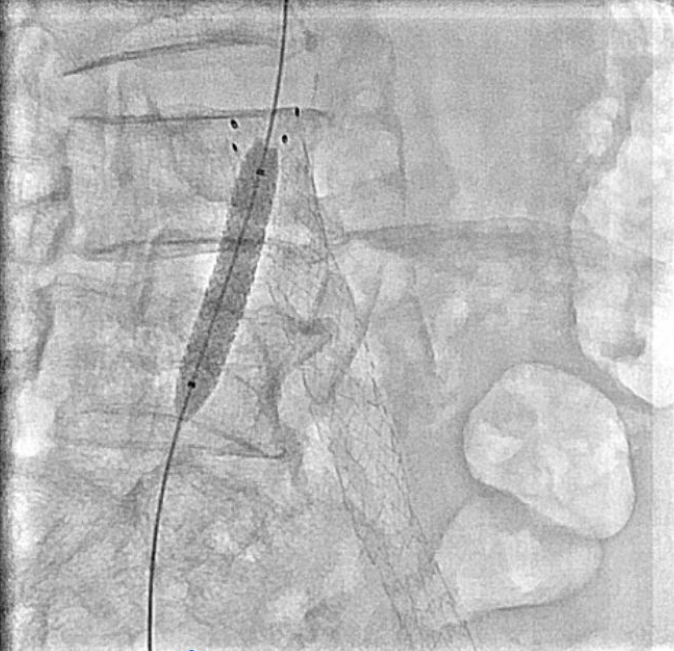

Venography showed occlusion of the right external and common iliac veins with collateral flow; popliteal and femoral veins were patent. A 6F sheath was placed in the right CFV, and a V-18 0.018 wire was advanced to the IVC. Attempts to traverse outside the prior left iliac-femoral stent for double-barrel reconstruction were unsuccessful, as the wire repeatedly entered the existing stent, likely due to complete apposition.The strategy was revised, and wiring into the IVC through a proximal stent strut was achieved. IVUS from the IVC to the RCFV confirmed severe compression at the right CIV ostium and proper wire position. A 10 ¡¿ 39 mm Abbott Omnilink balloon-expandable stent was deployed at the RCIV ostium and dilated to 10 atm. A kissing-balloon angioplasty was then performed with a 12 ¡¿ 40 mm Armada balloon from the LCIV and the RCIV balloon inflated simultaneously to 10 atm, restoring bifurcation geometry.A 14 ¡¿ 60 mm Bard Venovo stent was placed from the RCIV to the REIV and post-dilated with a 12 mm balloon to 10 atm. Final angiography showed widely patent, well-expanded stents with brisk antegrade flow into the IVC and no residual stenosis or thrombosis. Hemostasis was achieved with manual compression, and the procedure concluded without complications.